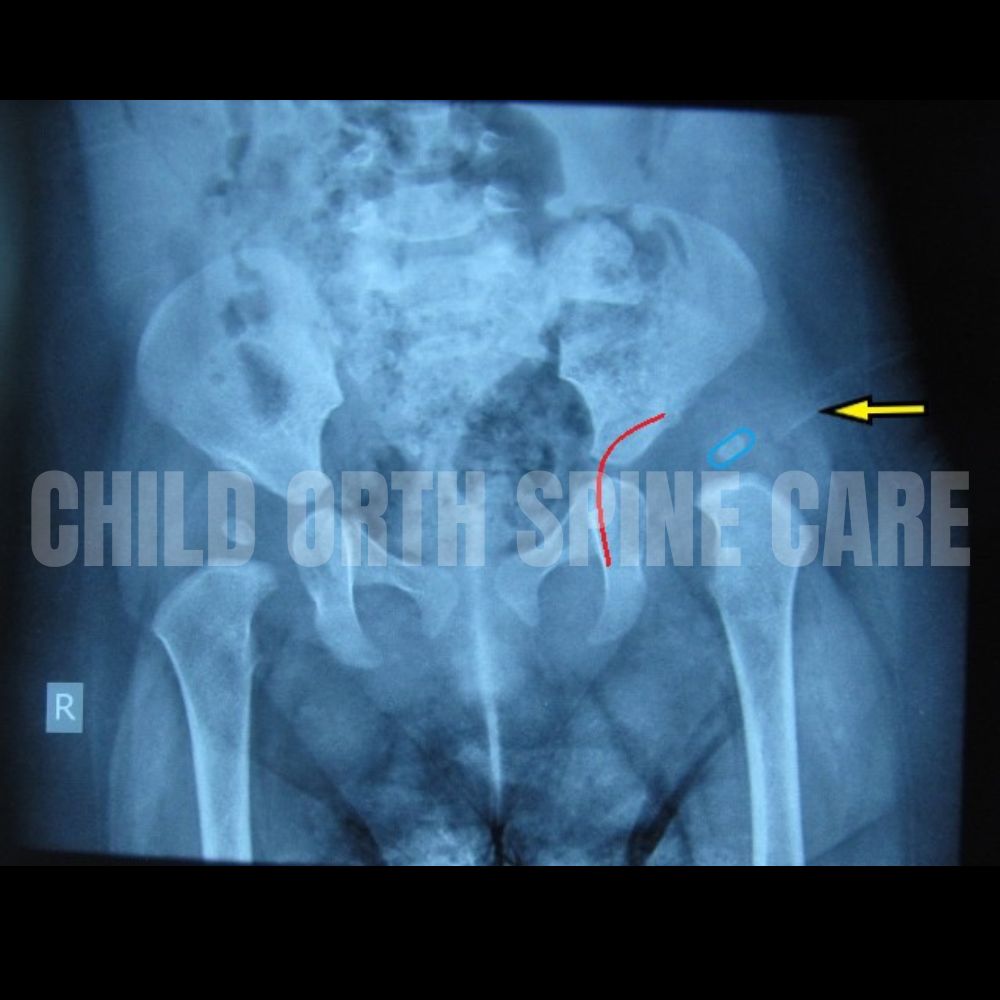

Left hip dislocation in a 7 month old/ Notice the ball of the thigh bone (blue ring) is out of the socket (marked in red ).